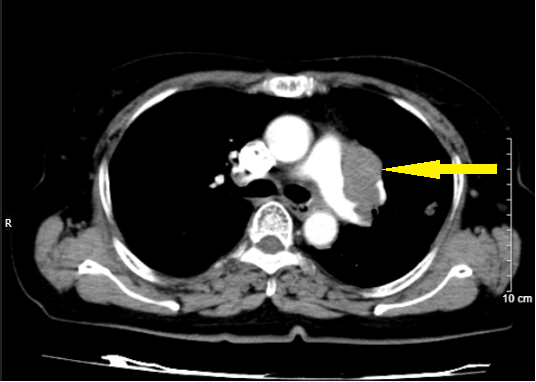

Hình 2: Hình ảnh trước điều trị (bên trái): Hình ảnh khối u và tổn thương di căn phổi cùng bên (mũi tên đỏ). Hình ảnh sau điều trị (bên phải): không còn khối u sau 3 chu kì điều trị

Hình 3: Hình bên trái (trước điều trị): Hình ảnh khối u (mũi tên vàng). Hình bên phải (sau điều trị): không còn tổn thương di căn phổi cùng bên sau 3 chu kì điều trị